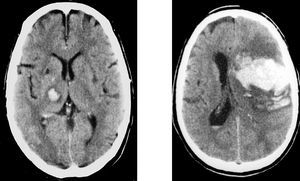

El 40% de las HIC son de localización lobar, la mayoría en los lóbulos parietal y occipital. En la HIC de localización lobar, aparte de la HTA, deben tenerse en cuenta otras etiologías, como malformaciones vasculares en pacientes jóvenes, metástasis, y la angiopatía amiloidea en pacientes ancianos (fig. 6).

Fig. 6. Hemorragia intracerebral. A la izquierda: hemorragia intracerebral profunda (cápsulo-talámica) hipertensiva. A la derecha: hemorragia intracerebral lobar.